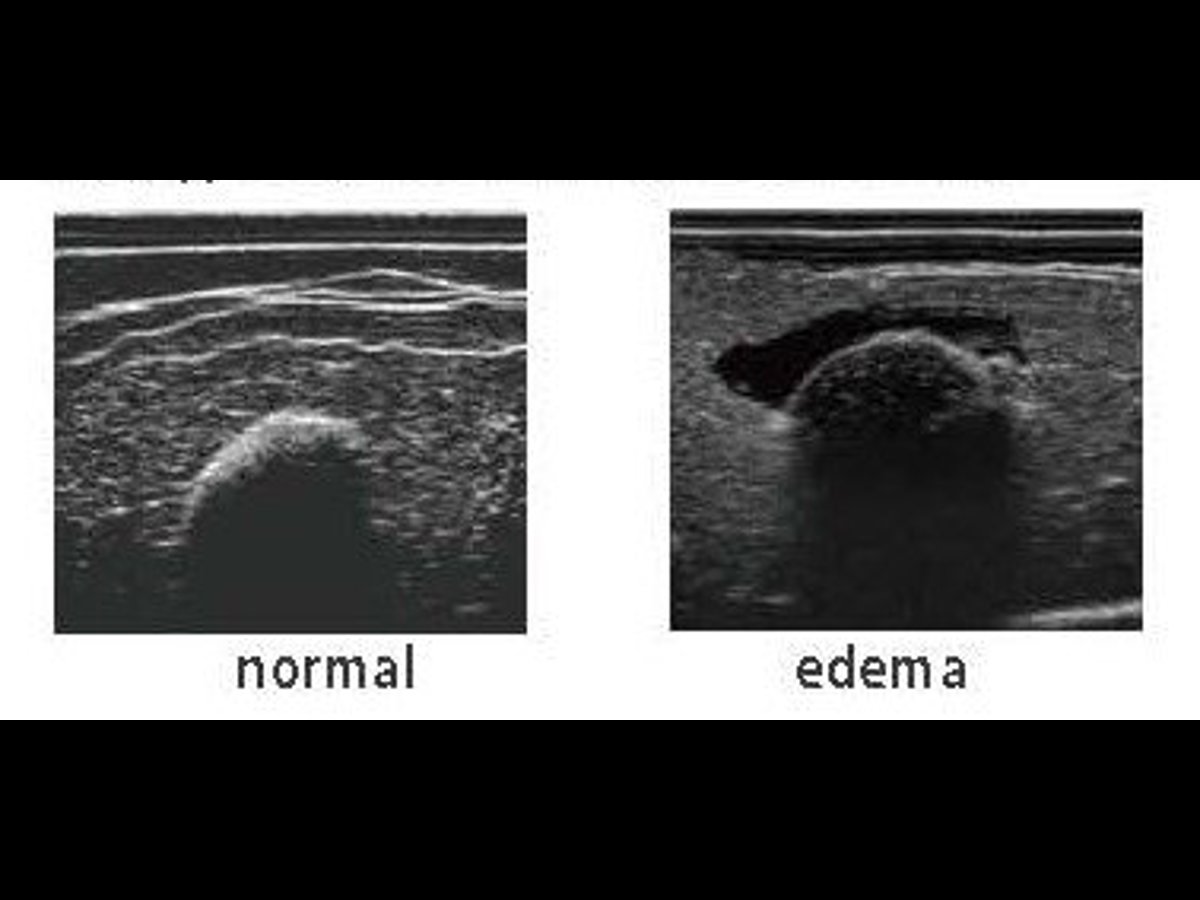

- Assessment of deep tissue by ultrasound (edema in the sciatic area)

- also includes two echo pads, one with edema, and one normal

- Ultrasound compatible sciatic inserts

- Sciatic pressure sores can be viewed under ultrasound